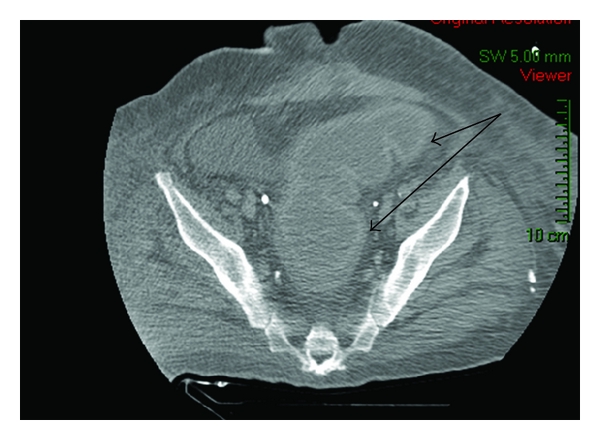

On a detailed workup of sepsis, stool sample cultures for Clostridium difficile toxins from the rectum and end ileostomy were performed. Diagnosis of colitis was made by a positive Clostridium difficile toxin in the rectal sample and was confirmed by CT findings of a thickened, dilated, and distended colonic wall (mucus fistula segment) (Figure 1). Clostridium difficile culture from the ileostomy was negative. Moreover, a pathological examination disclosed cecal perforation, acute peritonitis, and a tubulovillous adenoma in the cecum which was located 3 centimeters distal to the point of perforation. No evidence of colitis was encountered in the removed segment of the right colon.

Primary diagnosis of Clostridium difficile colitis is based on the presentation of diarrhea with positive toxin stool cultures. Endoscopic examination may also detect typical macroscopic pseudomembrane findings of the colonic wall. CT findings can be helpful in confirming the diagnosis, showing thickening, dilation, and potential perforation of the colon [2, 5–7].